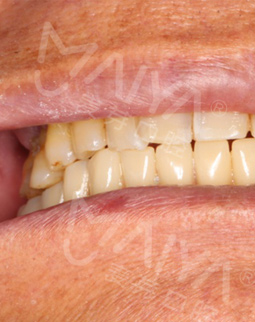

要说我的牙齿问题,得从五年前说起,那时候因为对缺牙的不重视导致满口牙都受到影响,逐渐掉落,去年在不得已的情况下按照了假牙。但没想到,自从安装假牙后我连一点硬东西都吃不了,很多美食都无法享受,最主要的是卡环的钩子导致我张口就感到疼痛,这个假牙没用两三次就扔掉了。不由感叹一声,本来想要在退休后感受一下慢生活,谁知道连基本的饮食都成了问题。

当然我还顺带参加了一下他们的活动,比如分享会、疑难缺牙工程等,跟同样缺牙的老伙计们讲了一下我的故事,分享了一下种牙经历,不得不说自从种完牙后生活发生了巨大的变化,不仅现在可以吃小龙虾、大闸蟹、排骨这些硬菜,还有一些“硬”水果现在也可以吃了,不再以稀饭和面条为主,生活又开始变得有滋有味,现在我的朋友都说我开朗了不少,之前合影都是抿着嘴,现在拍照都是哈哈大笑。